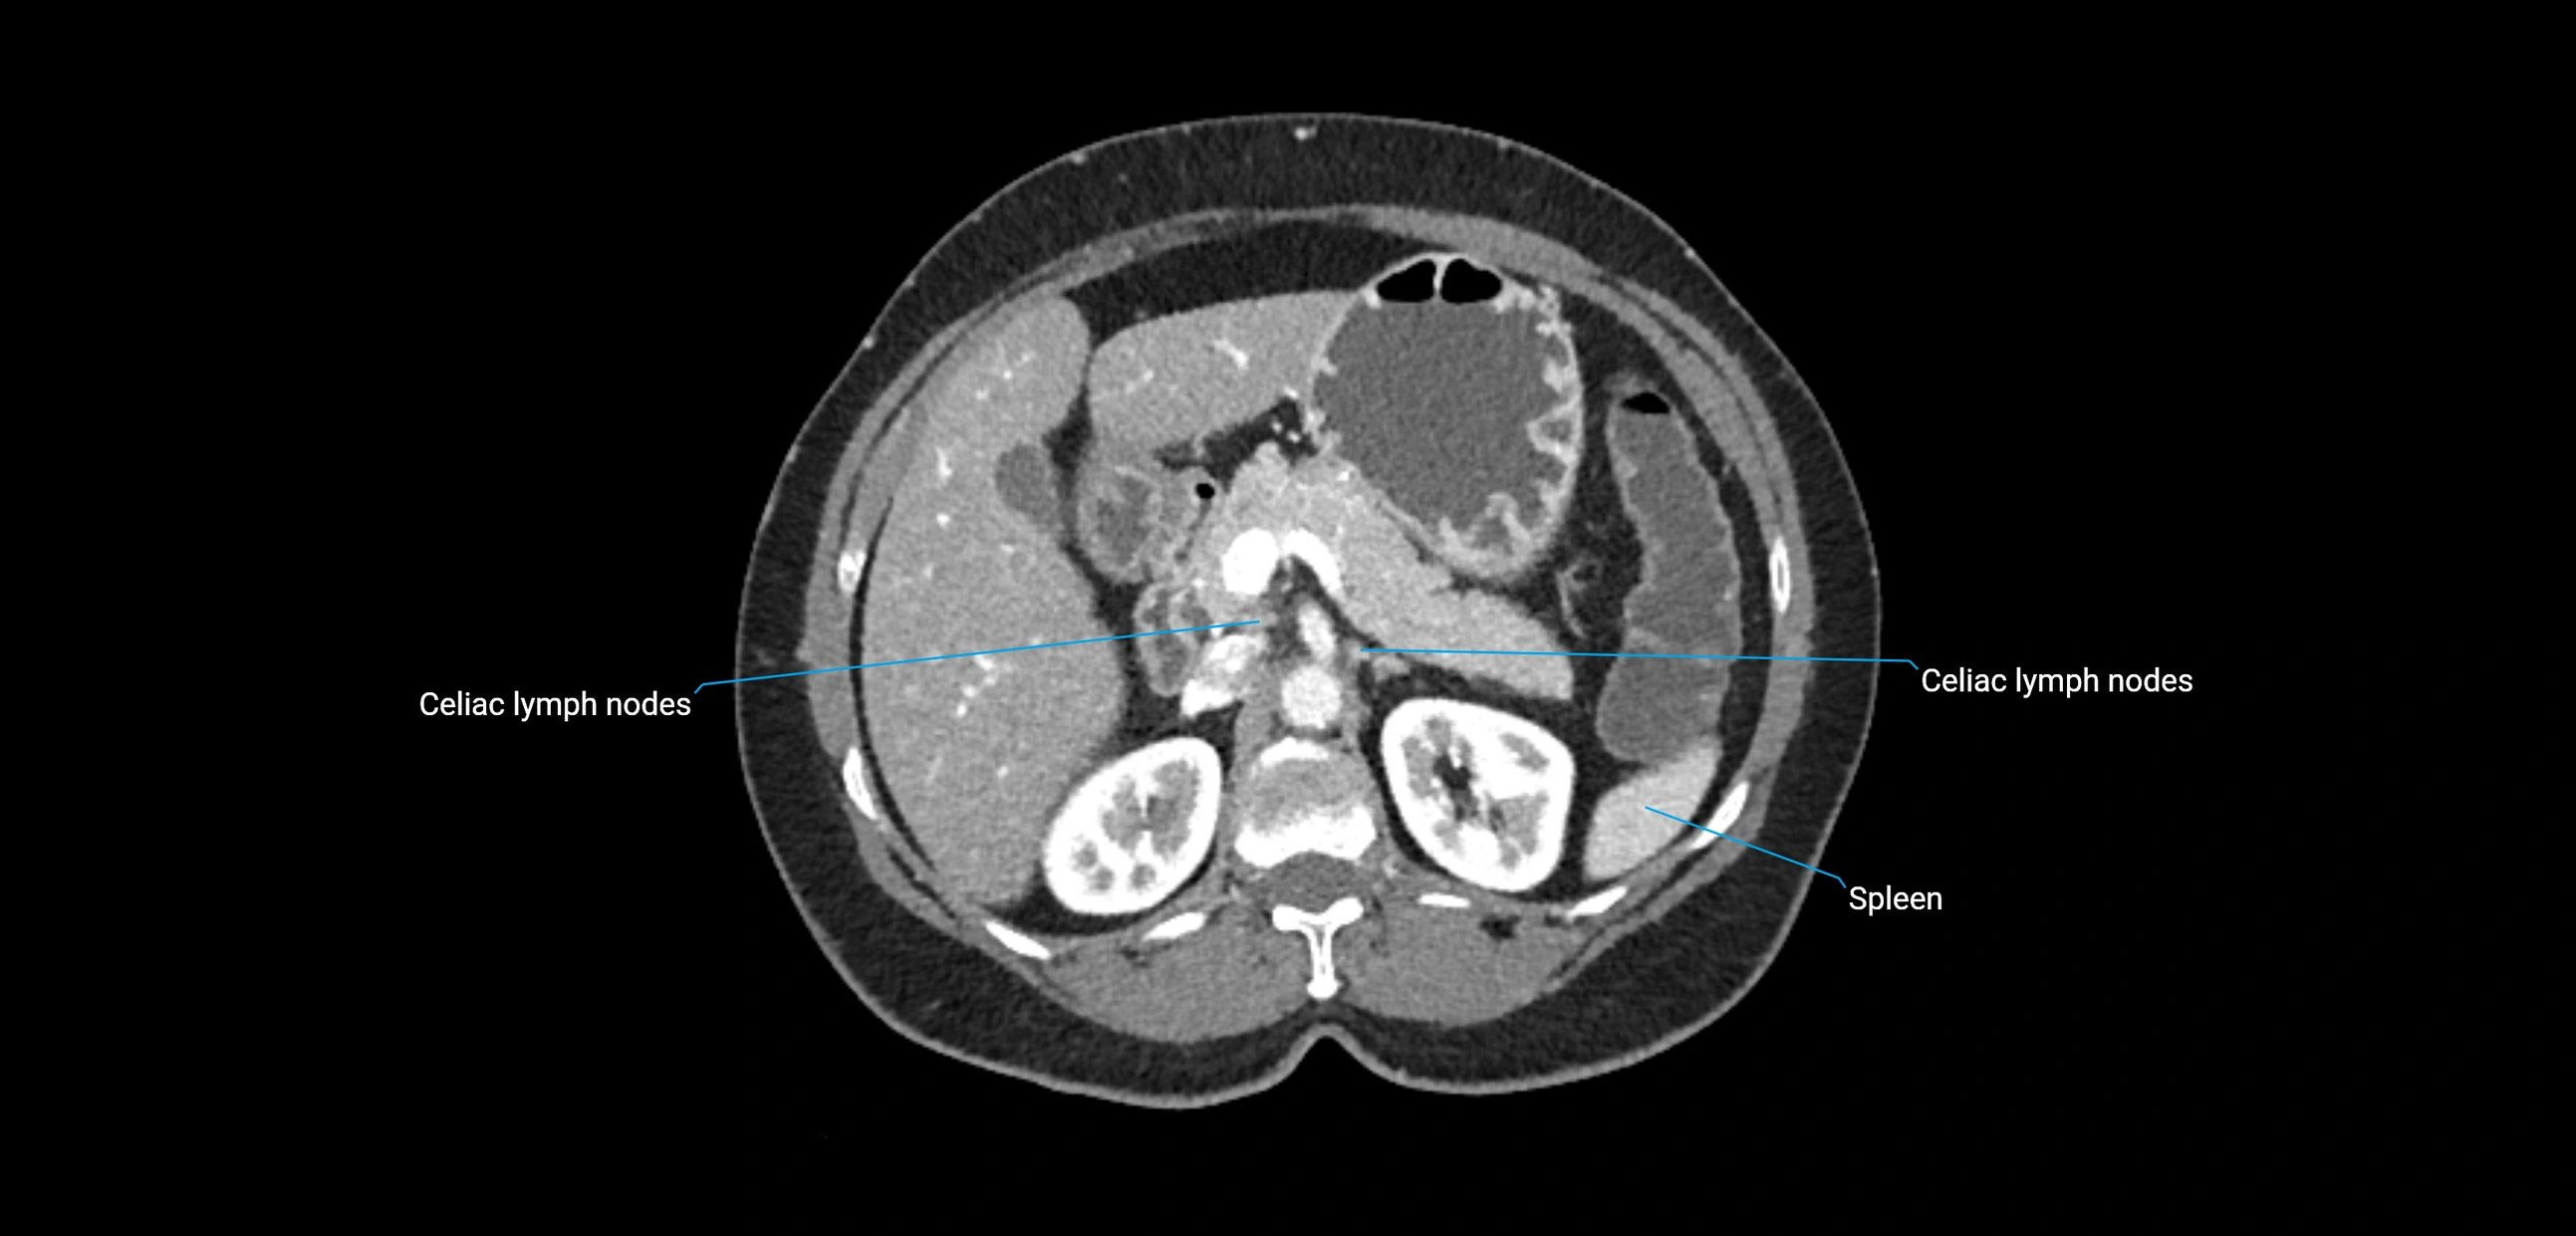

CT image

image